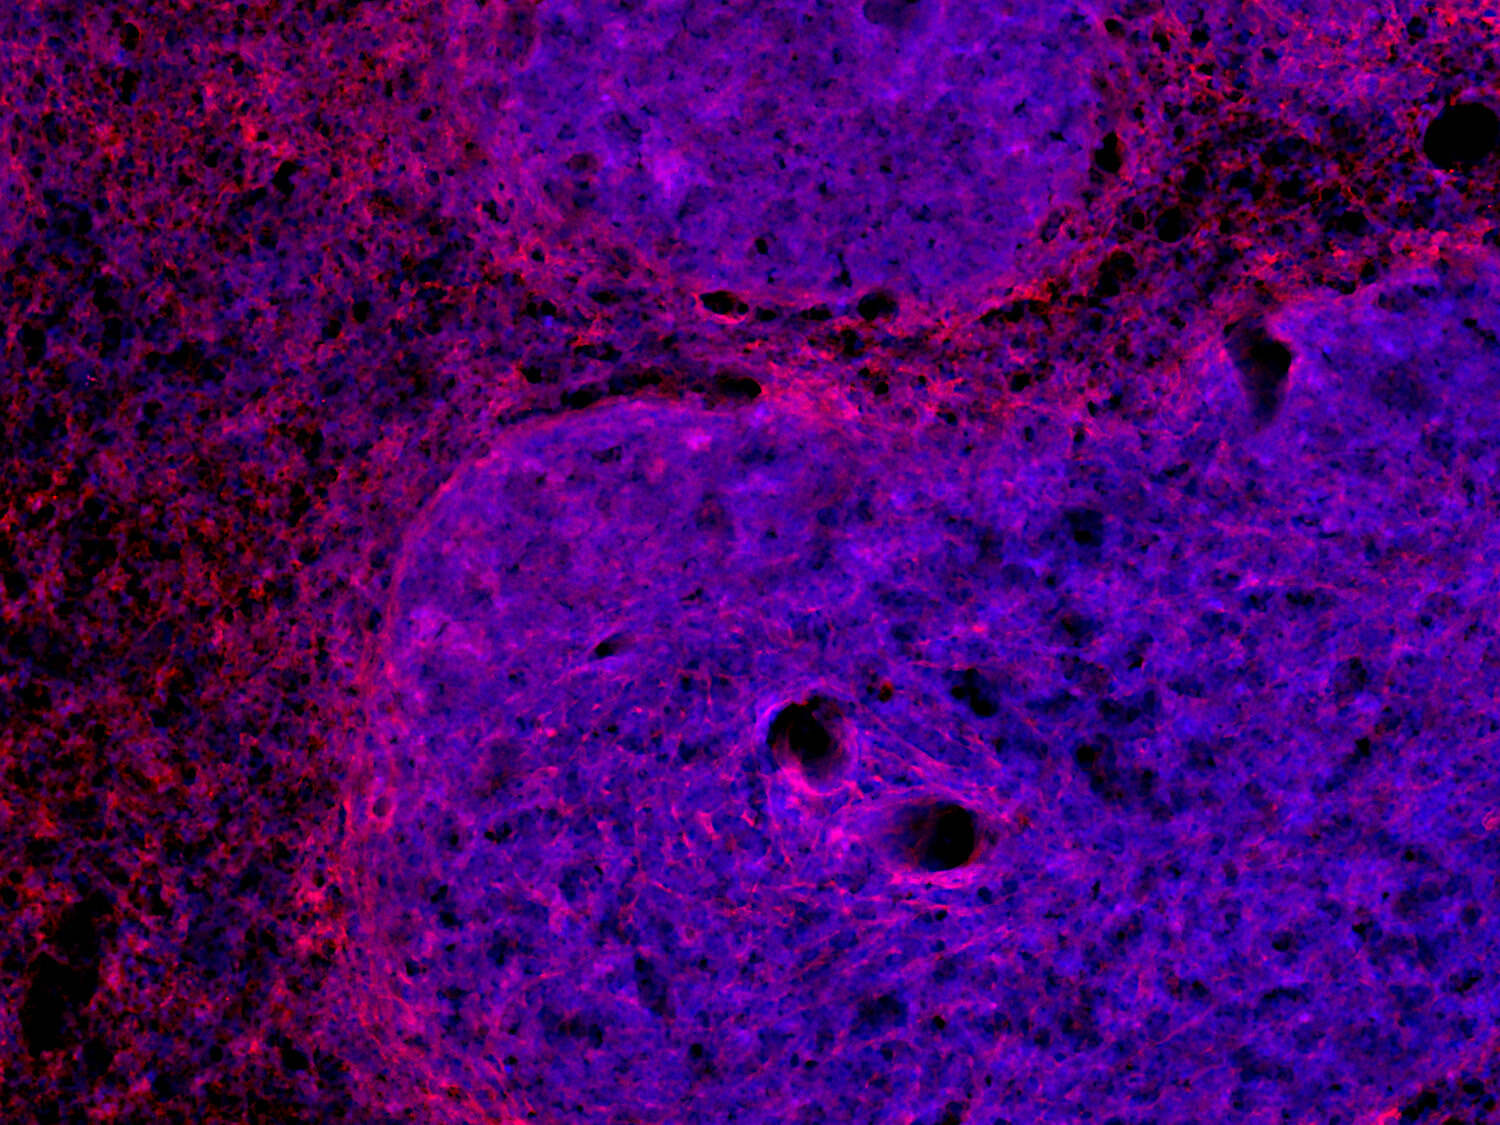

IHC: 1 : 500 (see remarks) gallery

Immunohistochemistry (IHC) on 4% PFA perfusion fixed tissue with 24h PFA post fixation. Immunoreactivity is usually revealed by fluorescence or a chromogenic substrate. Some antibodies require special fixation methods or antigen retrieval steps. For details, please refer to the ”Remarks” section.

IHC: Antigen retrieval with citrate buffer pH 6 is required.

Increased VCAM1 expression in a mouse liver infected with Toxoplasma (T.) gondii